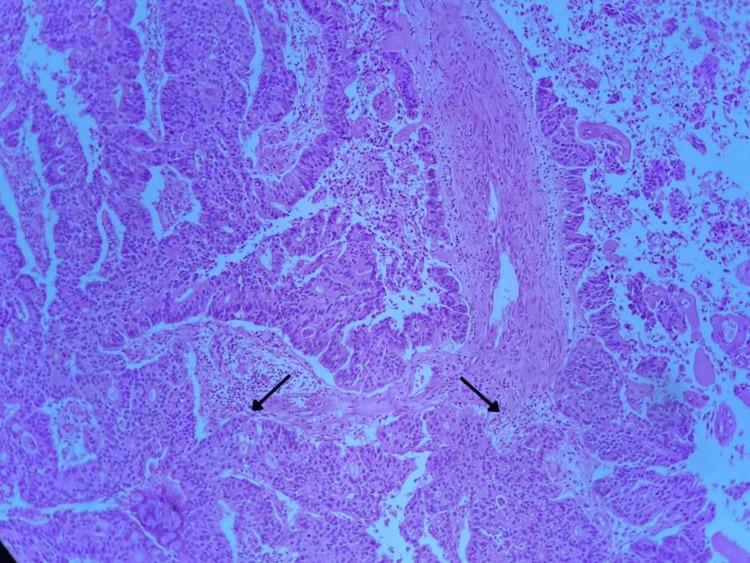

Urachal carcinoma is an uncommon malignancy with a peculiar biomolecular characterization and therefore a complex approach. It was incorporated by the World Health Organization in 2004 in the tumors of the urinary system classification. This neoplasm is generally diagnosed in advanced stages. The standard treatment is surgical, however, due to the rarity and relatively late clinical manifestation of urachal carcinomas, the survival data are mostly case reports, as well as information about medical-surgical treatment based on evidence. The data used were extracted from both the physical and electronic clinical records. Among atypical presentations reported in the literature, we report a case of urachal adenocarcinoma with simultaneous glomerulonephritis as a paraneoplastic syndrome of which there is no report to date. Surgery was carried out in our patient, unfortunately with lifetime morbidity from kidney function replacement secondary to kidney function damage by glomerulonephritis, despite previous immunosuppression treatment for rapidly progressive glomerulonephritis. It is worth mentioning that if the initial diagnosis represents a clinical challenge, treatment is even more complex, given the little information that currently exists about it. Urachal carcinoma is a diagnostic and treatment challenge. Up to now, surgery has been the treatment of choice in localized or locally advanced disease, however, with a high morbidity for the patient.

https://cdn.ncbi.nlm.nih.gov/pmc/blobs/be75/11164558/5feb140fecc9/cureus-0016-00000060106-i01.jpg